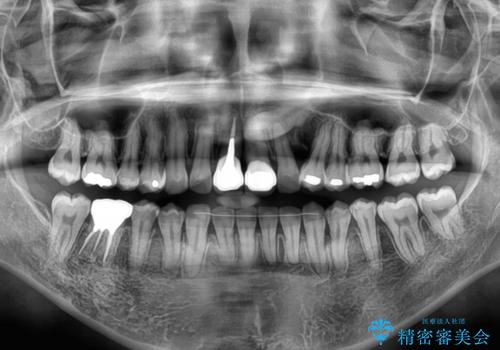

- 前歯のデコボコと、着色が著しい保険診療の前歯クラウンを気にして来院された患者様です。

左上の犬歯が埋伏しており、CT画像より萌出は困難と判断されたため、残存している歯にて歯列と咬合を整えることとしました。

マウスピース装着は煩わしいとのことで、表側のワイヤー装置にて矯正治療を行うこととしました。

前歯のクラウンは変色が顕著なため、矯正治療後にオールセラミッククラウンによる補綴治療を行うこととしました。

前歯のクラウンは、歯肉内深くに削り込まれており、歯肉の炎症が継続していたため、矯正治療後に歯周外科処置を行い、歯肉の腫れを改善させました。